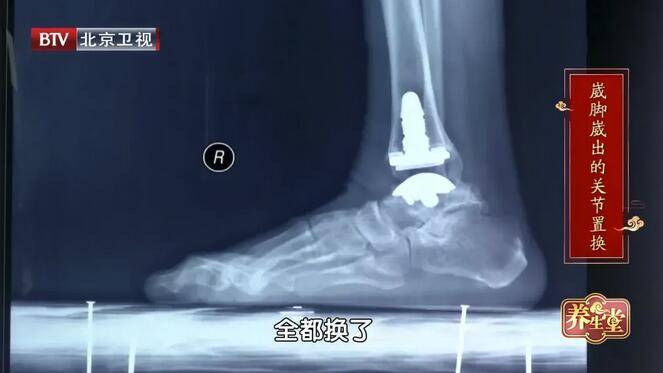

恒叔叔 , 71岁 , 无意中感觉右脚不吃力了 , 时不时的就会崴脚 , 即便自己已经很小心了 , 一年还是能崴脚七八次!右脚发生严重变形 , 穿袜子、穿鞋都困难 , 直到出现无法缓解的疼痛 , 恒叔叔才到医院去治疗 , 医生告诉他只能做踝关节全置换 , 才能彻底解决问题 。

髋、膝、踝应该在一条直线上 , 脚踝是基础 , 任何足部的变形都会影响到整个身体的稳定 。 恒叔叔就是经常崴脚导致足弓塌陷 , 久而久之就更容易崴脚 , 最后足踝变形不得不置换踝关节 。